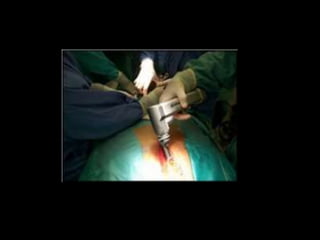

DIAGNOSTICO HISTOLOGICO

1. Mediastinoscopía cervical estándar

2. Mediastinoscopía infraesternal

3. Mediastinostomía anterior

4. PAAF

5. VATS

6. Esternotomía mediana

7. Toracotomía

MEDIASTINOSCOPIA

• Indicaciones

– Biopsia de ganglios

– Biopsia de tumores

– Timectomía (miastenia)

– Resección de adenoma paratiroideo ectópico

– Resección de quistes tímico

– Drenaje de colecciones cérvico-torácicas

MEDIASTINOSTOMIA

– Biopsias de tumores de mediastino anterior

– Biopsia de ganglios parahiliares y de la ventana

aortopulmonar

– Estadificación del cáncer pulmonar

– Complemento de la mediastinoscopía

VATS